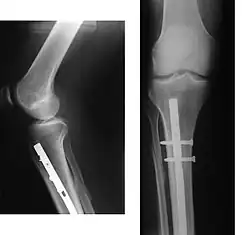

Since bone healing is a natural process that will occur most often, fracture treatment aims to ensure the best possible function of the injured part after healing. Bone fractures typically are treated by restoring the fractured pieces of bone to their natural positions (if necessary), and maintaining those positions while the bone heals. Often, aligning the bone, called reduction, in a good position and verifying the improved alignment with an X-ray is all that is needed. This process is extremely painful without anaesthesia, about as painful as breaking the bone itself. To this end, a fractured limb usually is immobilized with a plaster or fibreglass cast or splint that holds the bones in position and immobilizes the joints above and below the fracture.

When the initial post-fracture oedema or swelling goes down, the fracture may be placed in a removable brace or orthosis. If being treated with surgery, surgical nails, screws, plates, and wires are used to hold the fractured bone together more directly. Alternatively, fractured bones may be treated by the Ilizarov method, which is a form of an external fixator.

Surgery

Surgical methods of treating fractures have their own risks and benefits, but usually, surgery is performed only if conservative treatment has failed, is very likely to fail, or is likely to result in a poor functional outcome.[42] With some fractures such as hip fractures (usually caused by osteoporosis), surgery is offered routinely because non-operative treatment results in prolonged immobilisation, which commonly results in complications including chest infections, pressure sores, deconditioning, deep vein thrombosis (DVT), and pulmonary embolism, which are more dangerous than surgery.[43] When a joint surface is damaged by a fracture, surgery is also commonly recommended to make an accurate anatomical reduction and restore the smoothness of the joint.